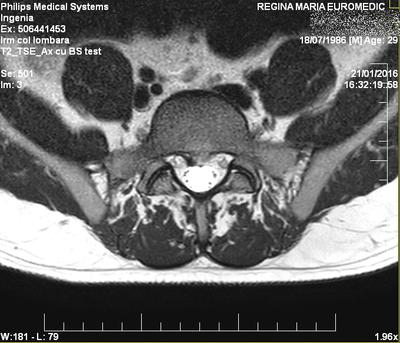

My name is Daniel, i am 30 years old, and i recently (about a month ago) had a lumbago episode due to my recurring lumbar disc hernia at L5-S1.

- My first HDL was in december 2010 (~5 years ago). MRI revealed a central disc herniation. Doctors said i should operate soon, but i didn't, i started taking antiinflamatory pills , rested flat in bed (and on the floor), and doing Williams exercises when my sciatica was feeling better.

Two years later, i have done another MRI which showed a small protusion only (the HDL was "gone"). I was feeling great!

Good luck, Daniel. I hope this contributes. It's not a large herniation.